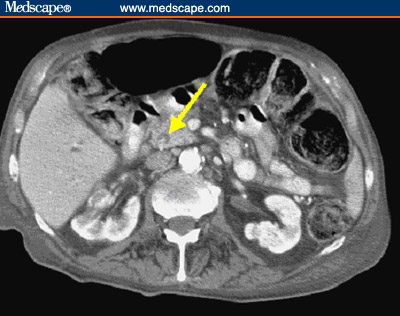

Tomografia computerizzata l'uso della TAC risulta efficace nell'indagine delle ostruzioni dell'albero biliare e nelle dilatazioni duttali siano esse exrta che intraepatiche.

Questa tecnica ha una sensibilità del 75-90% nella rilevazione dei calcoli della via biliare principale.Risulta utile per valutare il livello di ostruzione e fornisce informazioni morfologiche a riguardo delle strutture circostanti, particolarmente il pancreas.

Fig 4 Tac addome superiore- presenza di un voluminoso calcolo nel coledoco( freccia gialla)